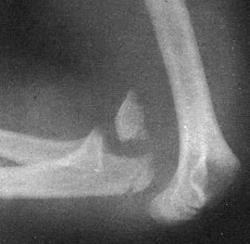

(Слева) На боковой рентгенограмме определяется задний вывих предплечья, в том числе локтевого отростка и головки лучевой кости. Большой отломок головки лучевой кости расположен кпереди от головки мыщелка плечевой кости.

(Справа) На передне-задней рентгенограмме определяется латеральное направление типичного вывиха. Видна вывихнутая головка лучевой кости с большим дефектом, вывихнутая локтевая костью и отломок перелома головки лучевой кости. Примерно 90% вывихов предплечья являются заднебоковыми по направлению. (Слева) На боковой рентгенограмме у подростка 11 лет определяется задний вывих локтевого и лучеголовчатого суставов. Отломки находятся в суставе.

2. Рентгенография при вывихе предплечья:

• Полная потеря сочленения между блоком и локтевой костью:

о Обычно смещение локтевой кости кзади

• Сопутствующий вывих головки лучевой кости

• Сопутствующие переломы